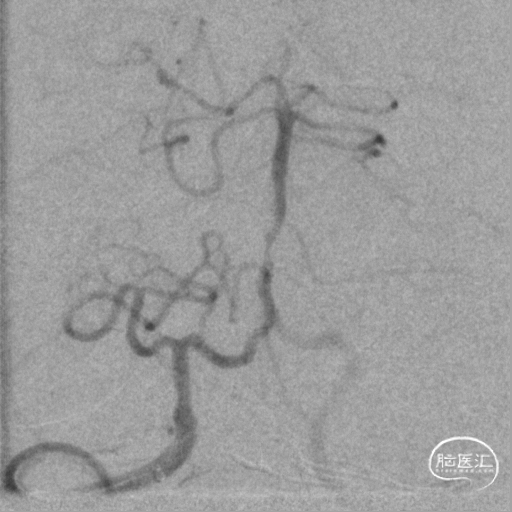

基底动脉中段重度狭窄,狭窄率约80%,双侧大脑后动脉可见显影。

将微导丝头端置右侧大脑后动脉,沿微导丝引入2.0*10mm球囊,小心扩张狭窄段,撤出球囊后造影,原有狭窄较前稍好转,沿微导丝引入支架用微导管置于基底动脉,撤出微导丝,保留微导管,沿微导管引入3.5*15mm Neuroform EZ支架,缓慢释放,复查造影,狭窄较前明显好转,支架贴壁良好。

术前DSA影像: